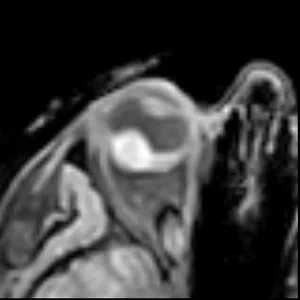

• T1 & T1Gd

T1 & T1Gd

Contrast enhanced scans to differentiate the lesion and retinal detachment.